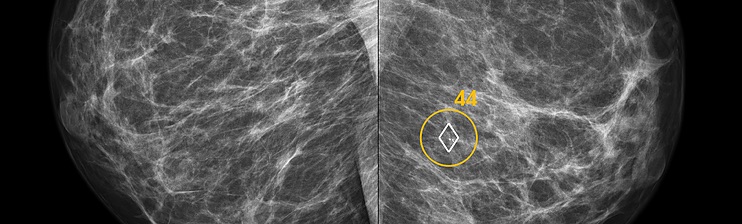

Photo courtesy of Hologic.

Utilizing state-of-the-art image analysis and deep learning technology, ScreenPoint’s Transpara automatically identifies soft-tissue and calcification lesions and combines the findings of all available views into a single cancer suspiciousness score. While calcifications are marked as in traditional computer-aided detection (CAD) systems, only a small number of soft-tissue lesion marks are shown and are proven to have low false positive rates. However, readers can probe any suspicious image region for decision support to help determine whether further investigation is needed.